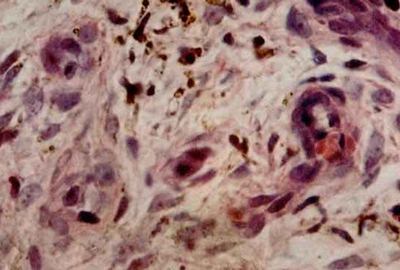

图注:aposis肉瘤 皮肤活组织检查 石蜡切片H-E染色 光镜(4×10)(10×10)(10×40)可见肿瘤组织中有许多新形成的血管,血管扩张,内皮细胞肿大突出于管腔内,红细胞外溢,含铁血黄素沉积。肿瘤由成纤维细胞、上皮样细胞淋巴细胞组成,并有大小不等、染色较深的圆形、椭圆形细胞。